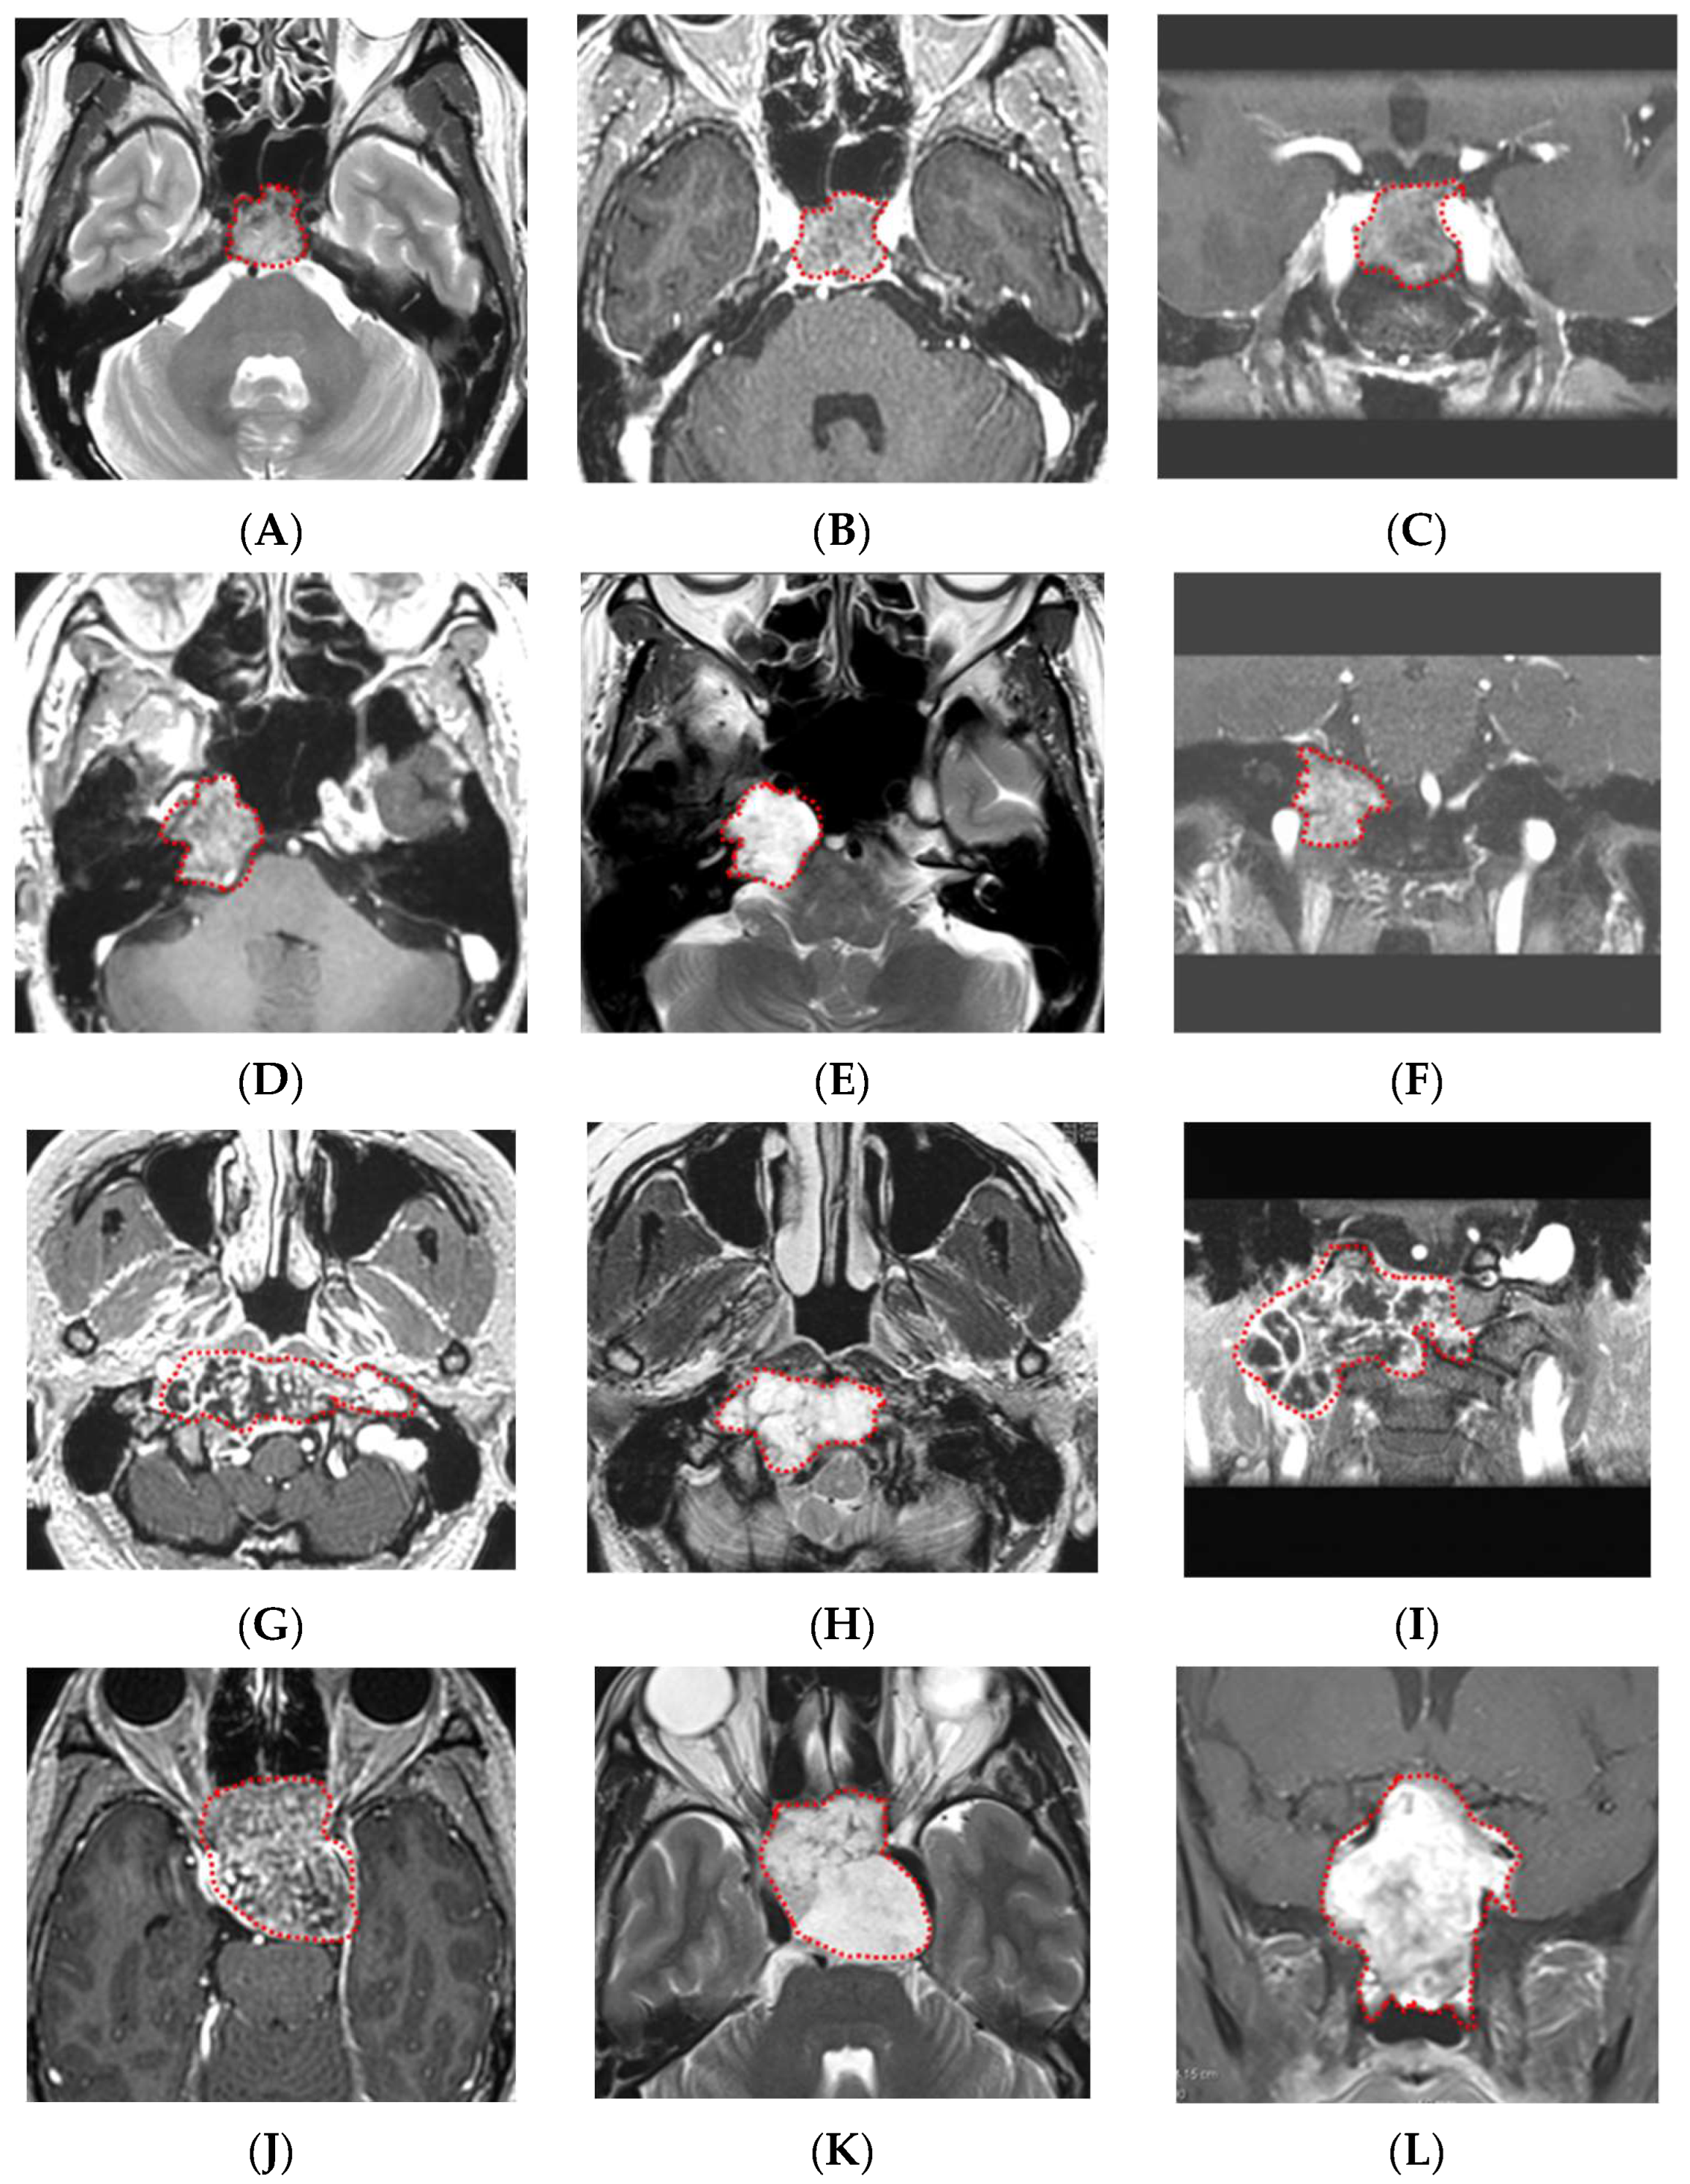

2.1. Cases and Magnetic Resonance Imaging (MRI) Sequences

- Two types of MR images were acquired for the preoperative evaluation: T2-weighted images (T2) and T1-weighted images with gadolinium enhancement (GdT1).